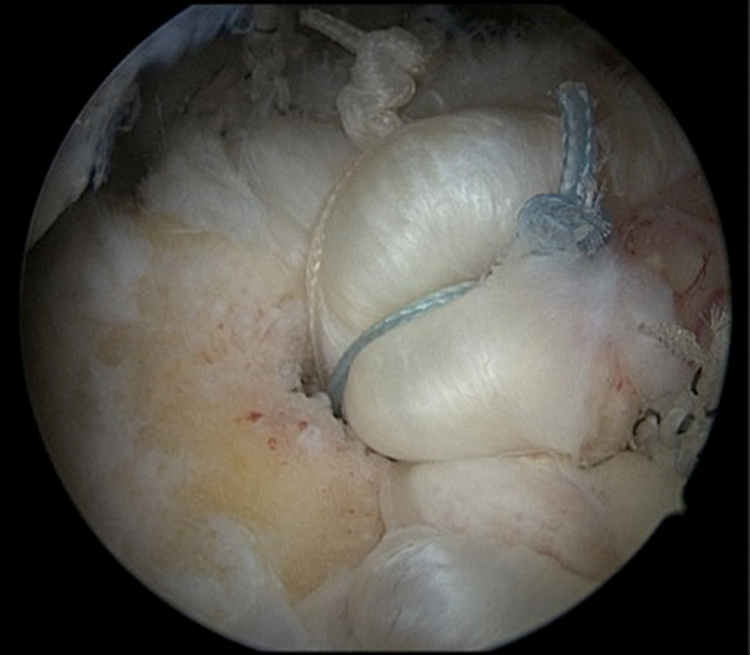

Single-Row Repair With Triple-Loaded Anchors

Single-row rotator cuff repairs were performed by placing several metal 5.5-mm corkscrew suture anchors (Arthrex) loaded with three No. 2 FiberWire sutures (Arthrex). Suture anchors were placed at the most lateral aspect of the greater tuberosity to which the tear would mobilize. Either 2 or 3 triple-loaded suture anchors were utilized to repair the tendon. A mean 2.2 anchors were used for the posterosuperior component of the repairs. Sutures were passed as simple stitches in an anterograde fashion, taking an approximately 1.5-cm bite of tissue with each stitch. All stitches were tied with 2 half-hitches on the same post, followed by another half-hitch in the alternate direction on the same post and by 3 half-hitches in alternating directions and alternating posts (Figures 3 and 4). Schematics for both repairs are shown in Figure 5. All subscapularis repairs were upper rolled border tears fixated with a single-row technique with a single anchor and 3 simple stitches.

Full-thickness supraspinatus tear viewed from the lateral portal.

Arthroscopic single-row rotator cuff repair with triple-loaded anchors and simple stitches in which 3 sutures (blue, white, and striped) can be seen originating from the same anchor.